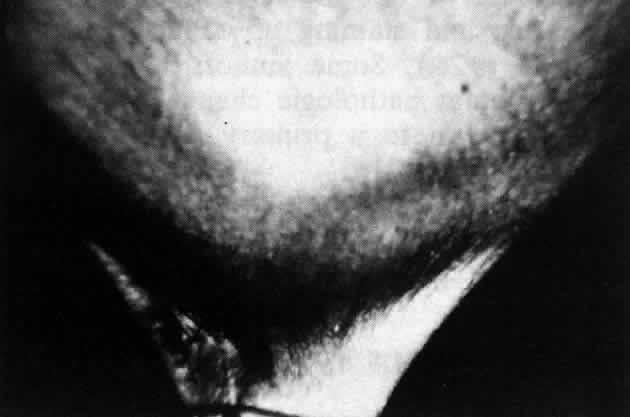

Pemphigus can be differentiated from bullous pemphigoid and from cicatricial pemphigoid on histologic and immunologic bases. Whereas the bullae in pemphigus are intraepidermal, those occurring in bullous pemphigoid and in cicatricial pemphigoid are subepidermal, between epidermis and dermis, or between mucosa and submucosa. Acantholysis is not present in the latter two conditions.5 In bullous pemphigoid and in cicatricial pemphigoid there are tissue-fixed immunoglobulins in the subepidermal basement membrane zone (Fig. 2).11 This is in contrast to the interepidermal fixation of antibodies (Fig. 3) seen in pemphigus (Table 1).

The diagnosis of OCP is extremely important, given the natural history of the disease, the effectiveness but potential toxicity of therapy, and the potential confusion in differentiation from other causes of chronic cicatrizing conjunctivitis (Table 2). The clinical diagnosis requires immunohistochemical confirmation prior to institution of therapy20; the diagnosis is confirmed by the demonstration of one or more immunoreactants at the epithelial basement membrane zone (see Fig. 2).